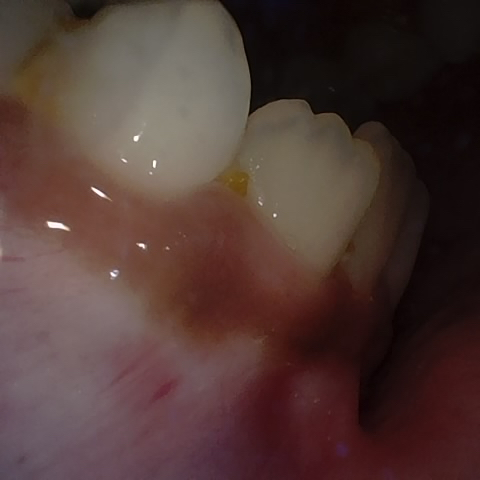

NHD27230

Annotated as "Good"

Original Image Rendering Image